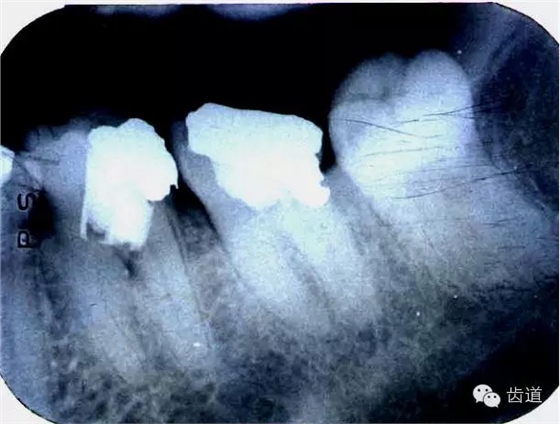

左上5牙頸部側(cè)穿

左下6底穿

左上6底穿

左上4鑄造樁側(cè)穿